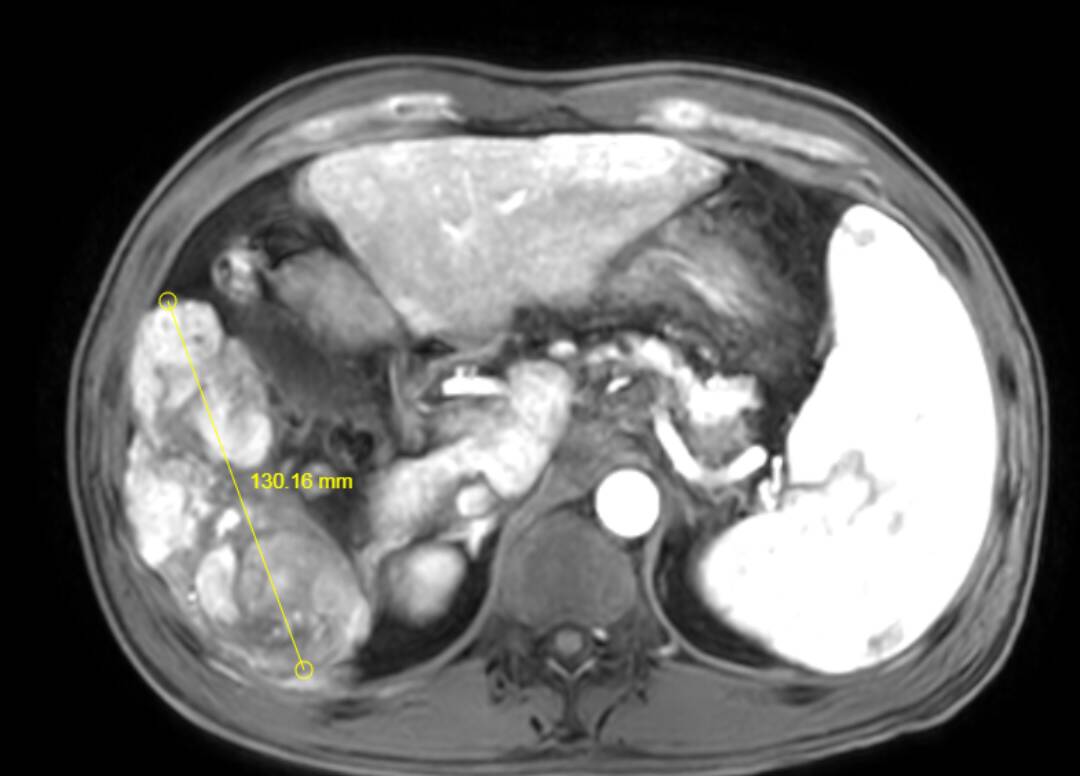

其中,成功为一名患者实施超大肝癌切除术,完整切除肿瘤大小达19cm×15cm,精准突破肝胆外科传统“手术禁区”,标志着普外二科在复杂肝胆肿瘤外科治疗领域迈上全新台阶。

此次切除的肿瘤体积巨大、血供丰富,与肝内重要血管、胆管粘连紧密,术中极易发生大出血、胆漏、肝功能衰竭等致命并发症。手术既要确保肿瘤完整根治、切缘干净,又要最大限度保留正常肝组织,难度与风险远超常规肝癌手术,对团队技术、经验与协作能力提出极高要求。

术前,科室联合影像、麻醉、重症监护、护理等多学科团队开展MDT会诊,全面评估肿瘤位置、大小、浸润范围及患者基础状况,精准规划切除路径与血管保护策略,反复推演手术流程,制定周密手术方案与应急预案,为手术成功筑牢坚实安全防线。

术中,手术团队在胡三元特聘专家与赵承乾科主任指导下,凭借精湛外科操作与丰富临床解剖经验,在高清手术视野下精细分离、逐层剥离、精准控切,妥善保护肝门部血管、胆管等关键结构,平稳完整剥离并切除巨大肿瘤,全程出血少、创伤可控,顺利完成高难度根治操作。